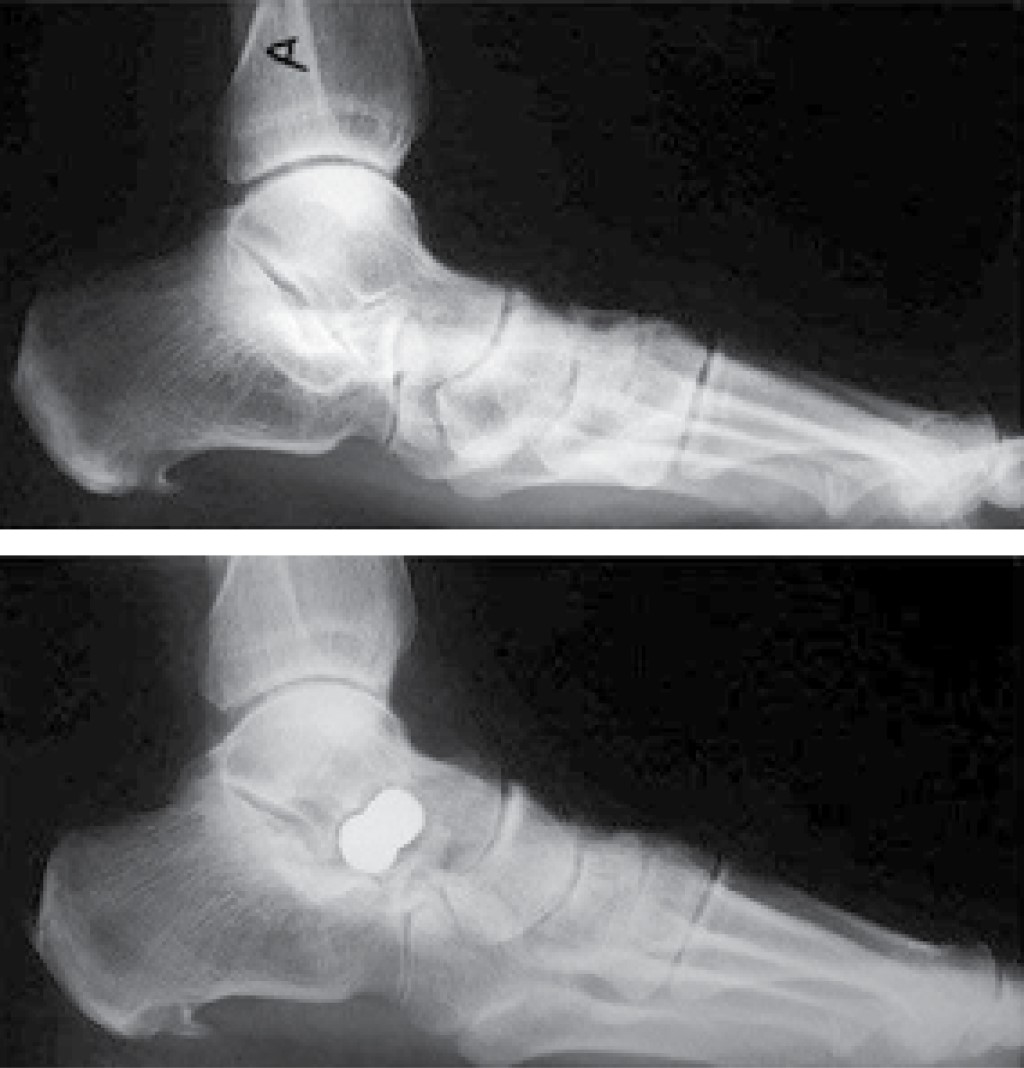

Figure 1

Figure 2

Figure 3

Figure 4

Figure 5

Figure 6

Figure 7

Figure 8

Figure 9

Figure 10

Figure 11